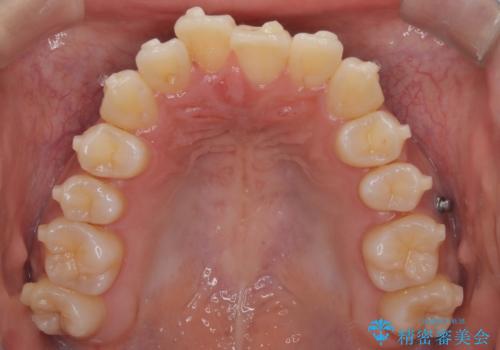

前歯の叢生・Ⅱ級咬合を改善|TADを用いた遠心移動+インビザライン矯正

- 前歯のガタガタと臼歯関係のⅡ級(上顎の歯列が前方にある状態)を改善するため、TAD(歯科矯正用アンカースクリュー)を使用したインビザライン矯正を計画しました。まずTADを上顎の適切な位置に設置し、それを固定源にして奥歯を後方(遠心)へ移動させ、十分なスペースを確保します。その後、インビザラインによるマウスピース矯正で前歯の歯列を整え、臼歯関係を正常化します。治療期間はおよそ1年半〜2年を想定しています。

前歯部の叢生(ガタガタ)と臼歯関係のズレを改善するため、抜歯をせずに奥歯を後方へ移動(遠心移動)させることを選択しました。TADという小型のアンカースクリューを顎骨に設置することで、確実かつ効率的に奥歯を後方へ移動させました。併せて透明で目立ちにくいインビザラインを用いることで、審美性を保ちながら治療を進めることが可能でした。患者様の負担が少ないマウスピース矯正と固定源のTADを組み合わせることで、抜歯することなく歯並びと噛み合わせを大幅に改善でき、大変ご満足いただけました。